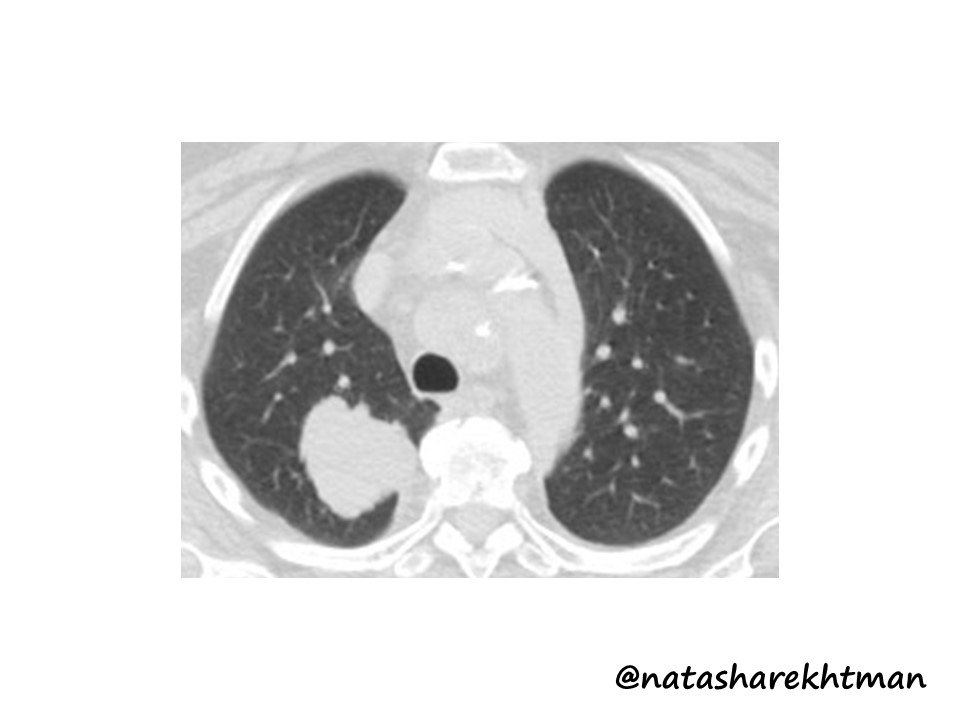

Hi all! Common #pulmpath scenario: adult W, smoker, 5 cm lung mass. No known Hx & no lesions elsewhere.❓for #pathologists: is IHC needed here or is this c/w lung primary based on clinical setting & histology? (obvious bait, but good real-life scenario to discuss) #natpathpuzzler

Lung lesion. What stains will you request #lungpath @ac_pathgal @raghupillappa @HansiniMD @SanicaBheleMD @NupursharmaMD @Sujata_path @JayaVen @SusanKarki777 @AlainCagaanan @Ramavid15 @Drsandeep89 @DonthiDeepak @DrNidhiKataria @DrGeeONE @kkuanMD @TheKarenPinto @ALBoothMD @Debdasmd